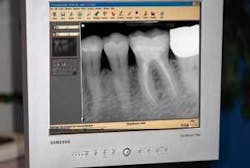

Quality digital X-rays cannot be overstated. Periapical radiolucencies and opacities are still the best indicators of a diseased tooth. Poor X-ray developing, improper angles, and faulty exposure settings all contribute to incomplete and unreliable diagnosis. Digital X-rays can help remove these errors, can be manipulated in the software to increase their diagnostic contribution, and the images have almost zero wait time. Perhaps the greatest advantage of all is that the digital image is usually seen on a 15 by 20 inch monitor instead of a 2 by 3 inch film on a view box (Fig. 1). It is certainly easier to diagnose from an image that is seven times larger with sharp detail.